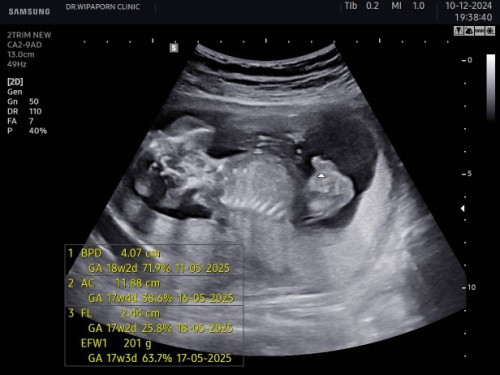

18สัปดาห์4วัน

ผู้ชายแหละแม่ เป็นแท่งเลย😆

แล้วคือใหญ่ด้วยนะแม่🤣🤣

มาเป็นแท่งเลยค่ะแม่

ชัดค่ะแม่